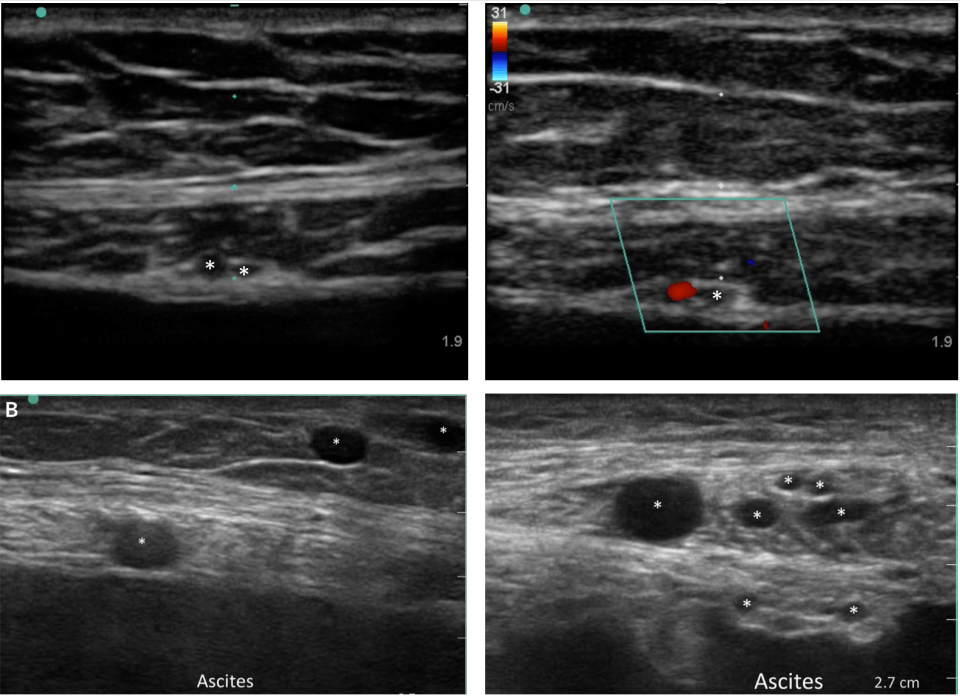

- Use the linear (vascular) probe to assess for subcutaneous vessels prior to needle puncture

- 1 institution found vessels in the path of their needle 10% of the time, and reduced major bleeding with routine use of the linear US probe7